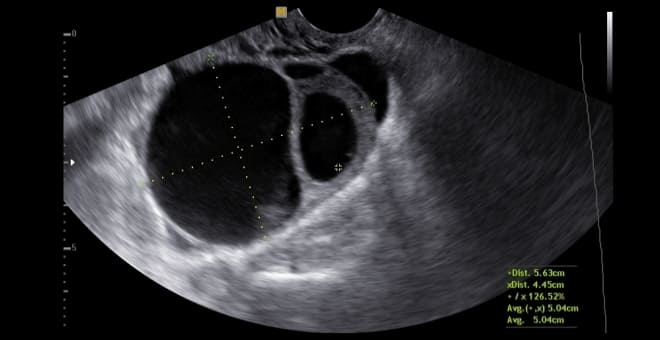

Это округлая, гипоэхогенная структура с толстыми стенками. Полость кисты четкая и гладкая, без каких-либо включений.

Обычно размер кисты желтого тела составляет от 4 до 8 см. Благодаря наличию пристеночного кровотока, на ультразвуковом исследовании она выглядит как огненное кольцо.